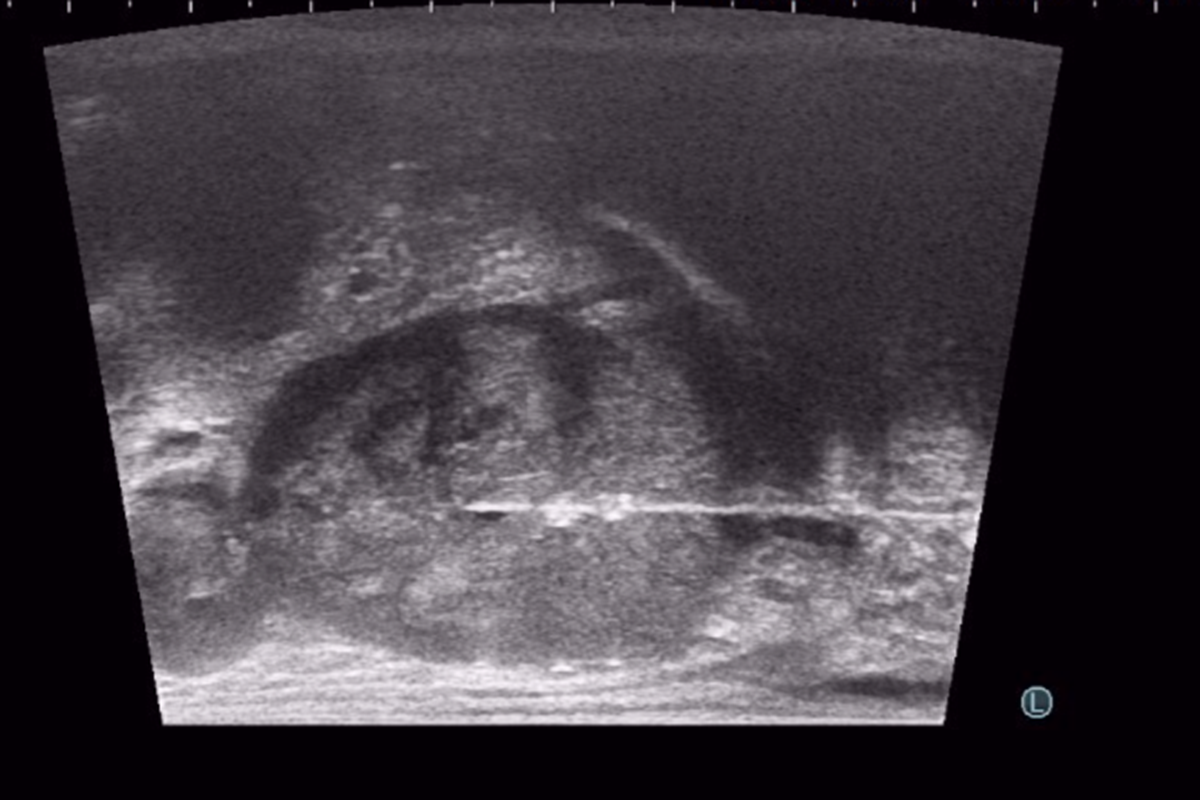

Başlığı makat bölgesine yerleştirdikten sonra, Ultrason’da prostat, TRUS biyopsi ultrason cihazından daha da net bir şekilde görülür. Bundan sonra, çok ince bir iğneyle perine adı verilen, makat ile yumurtalıklar arasındaki cilt bölgesine uyuşturucu ilaç verilir. Cilt uyuştuktan sonra aynı ince iğne daha içeri doğru ilerlenip, prostatın çevresine de uyuşturucu ilaç (lokal anestezi) yapılır. Böylece giriş alanı ve prostatın tamamı uyuşur ve işlemin bundan sonraki kısmını hasta en fazla sinek ısırığı gibi hafif bir acı olarak hisseder. Bu aşamada, ülkemizde çok az merkezde uygulanan, koaksiyel iğne ile biyopsi işlemini yapmaktayız. Ülkemizde birçok merkezde TP prostat biyopsisi yapılmaktadır. Ancak çoğunda, prostattan alınacak her parça için iğne perine adı verdiğimiz bölgeye tekrar tekrar girip çıkmaktadır. Bu da hem hastaya ağrı vermekte, hem de yan etki risklerini arttırmaktadır. Bu yöntemle yapılan TP biyopsi işlemleri ağrılı olduğu için hastanın uyutulması gerekmekte, bu da işlemin ücretini ve süresini arttırmakta ve anestezinin ek yan risklerini getirmektedir. Bizim uyguladığımız tek iğne yönteminde ise, koaksiyel iğne adı verilen bir iğne, uyuşturucu yapıldıktan sonra perinenin bir tarafından içeri yerleştirilir. Bundan sonraki parçalar, biyopsi iğnesi bu koaksiyel iğnenin içinden geçirilerek alınır. Böylece, ciltten sadece tek bir iğne girişi ile, prostatın bir tarafındaki tüm parçalar alınabilir. Bu yöntemde iğne ağrısı olmadığından, lokal anestezi ile uygulanmaktadır. Prostatın diğer tarafı için de tek bir iğne girişi kullanılır. Böylece, sadece iki iğne girişi ile, prostatın tamamından istediğimiz sayıda parça alabilmekteyiz. Temiz biyopsi işlemi yaklaşık 20 dakika kadar sürer ve yukarıda da bahsettiğimiz gibi, hastamız çok az ağrı hissederek işlemi tamamlar.